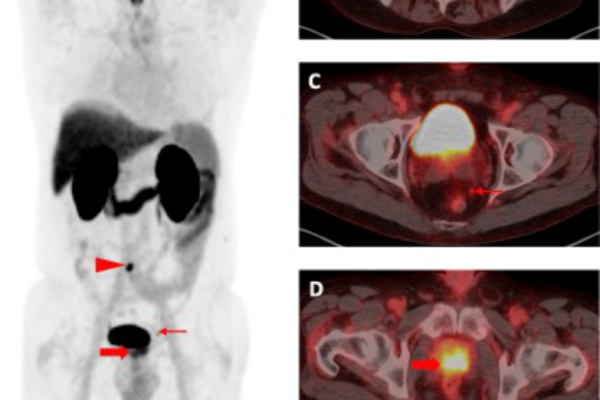

68-Ga PSMA PET-CT is an advanced molecular imaging technique specifically designed for detecting prostate cancer. It targets the Prostate-Specific Membrane Antigen (PSMA), a protein that is highly expressed on prostate cancer cells. This scan offers exceptional sensitivity and accuracy, even at very low PSA levels, making it valuable for both initial staging and identifying recurrence. It also plays a critical role in guiding treatment decisions, especially for patients being considered for PSMA-targeted therapies.

Key Indications:

• Initial staging of high-risk prostate cancer

• Detection of biochemical recurrence after surgery or radiation

• Evaluation of metastasis before or during treatment

• Selection for PSMA-targeted radionuclide therapy